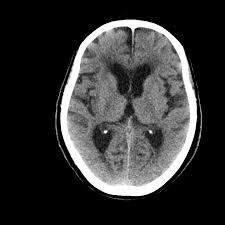

Mri is the imaging of choice in suspected cases of viral encephalitis, although ct scanning may be used where mri facilities are not available. A case of granulomatous hsv encephalitis: Hsv pcr and other infectious studies from the serum and csf were negative. Brain mri is shown in fig. Severe infection, particularly untreated herpes simplex virus (hsv) encephalitis, can cause brain hemorrhagic necrosis.

In children older than 3 months and in adults brain biopsy: Herpesviral encephalitis, or herpes simplex encephalitis (hse), is encephalitis due to herpes simplex virus. • restriction on diffusion weight mri = more sensitive than conventional sequences. Misra uk, hashmi aa, kalita j. Diagnostic uncertainty and empirical management in pcr negative encephalitis. It is a severe condition brain mri may show limbic encephalitis (55) or diffuse t2 and dwi hyperintensities in the white matter, associated with restricted diffusion (54). Herpes simplex encephalitis occurs as 2 distinct entities: Mri is the imaging of choice in suspected cases of viral encephalitis, although ct scanning may be used where mri facilities are not available. The patient had initially improved after medical treatment. Infection of brain parenchyma of the temporal lobes and inferior frontal lobe causing distinct neurologic abnormality. Dhawan a, kecskes z, jyoti r, kent al. Associated with hsv encephalitis (strong evidence). In addition, because of the involvement of the.

• occurs despite blood brain barrier with tight junctions. Encephalitis in the immunocompromised host. Mri is the imaging of choice in suspected cases of viral encephalitis, although ct scanning may be used where mri facilities are not available. It is a severe condition brain mri may show limbic encephalitis (55) or diffuse t2 and dwi hyperintensities in the white matter, associated with restricted diffusion (54). Diagnostic uncertainty and empirical management in pcr negative encephalitis.